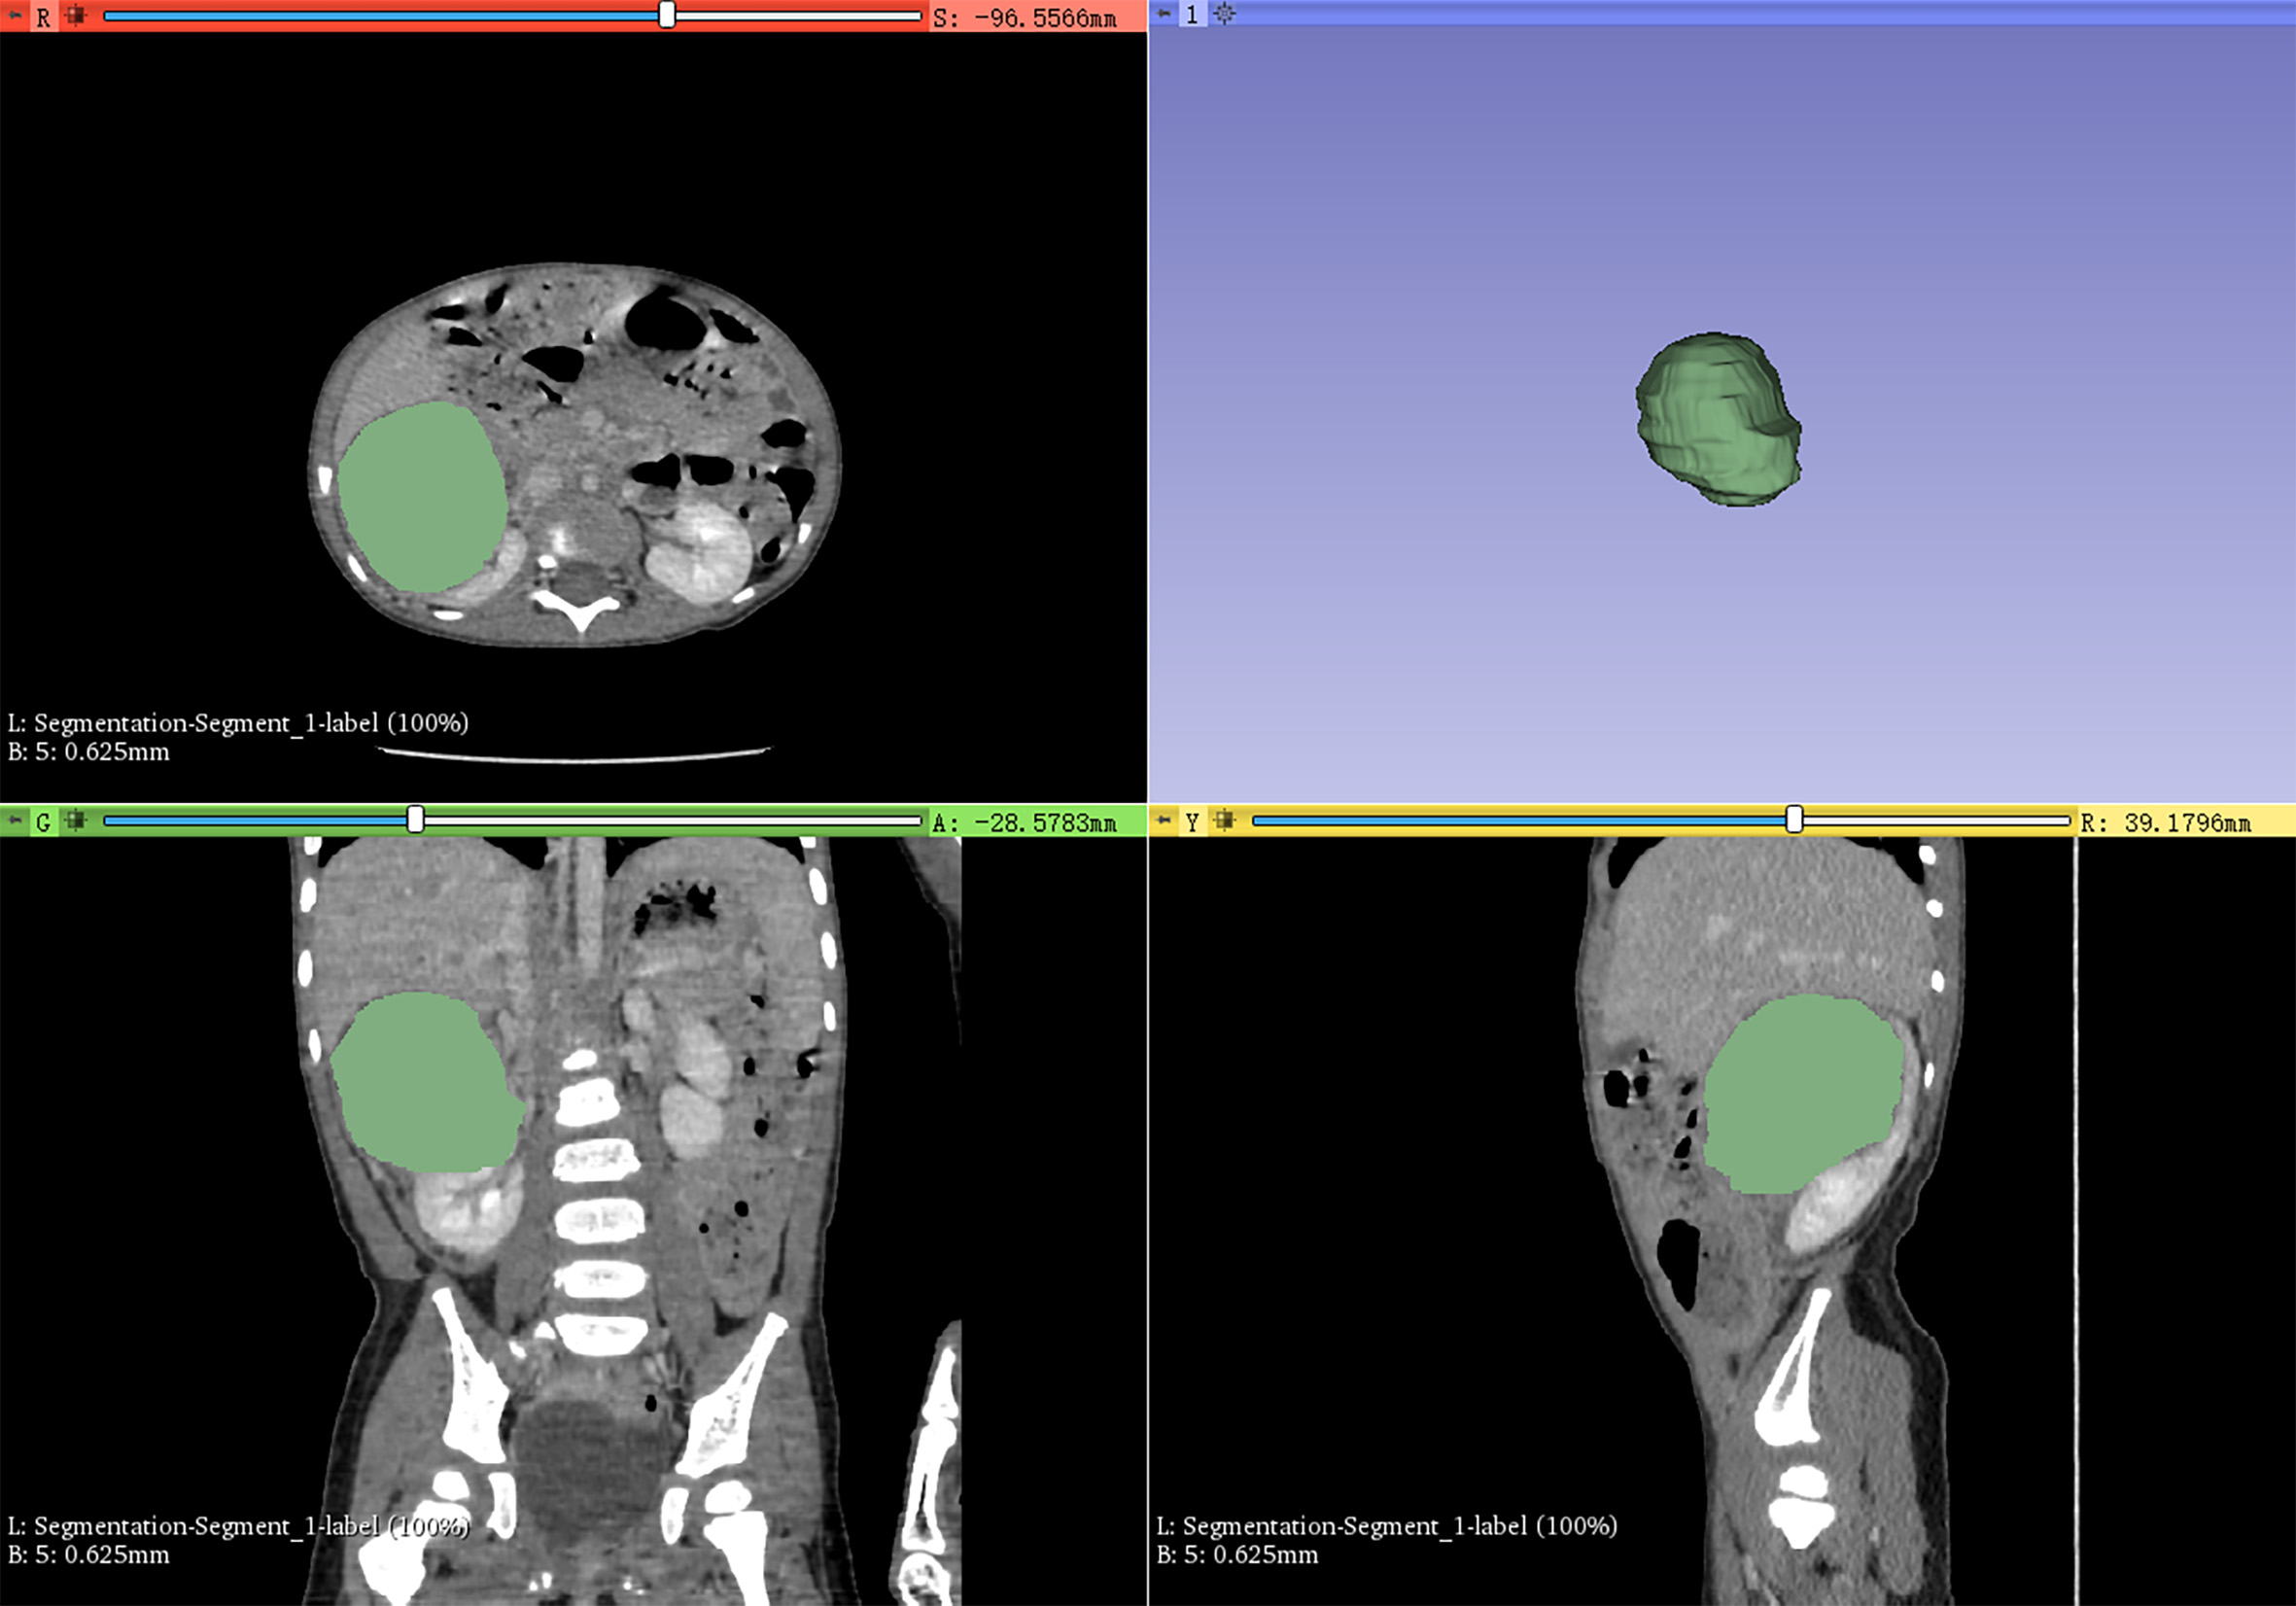

Volume of interest (VOI) including the whole mass of each nephroblastoma patient was segmented according to radiologists’ delineation (Figure 1), then, VOI of all the images were resampled and gray-level normalized by PyRadiomics before feature extracting. We utilized the nearest neighbor algorithm to interpolate each VOI into isotropic data. The voxel spacing of our isotropic data was set to 1×1×1 mm3, 3×3×3 mm3, or 5×5×5 mm3.

Figure 1

3D-Slicer was used to semi-automatically delineate the whole mass as the volume of interest for radiomics feature extraction.